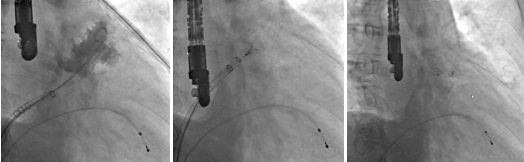

術(shù)前左心耳CT重建左心耳形態(tài)

?????? 左心耳造影圖像???????左心耳封堵器釋放前?????? 左心耳封堵器成功釋放后